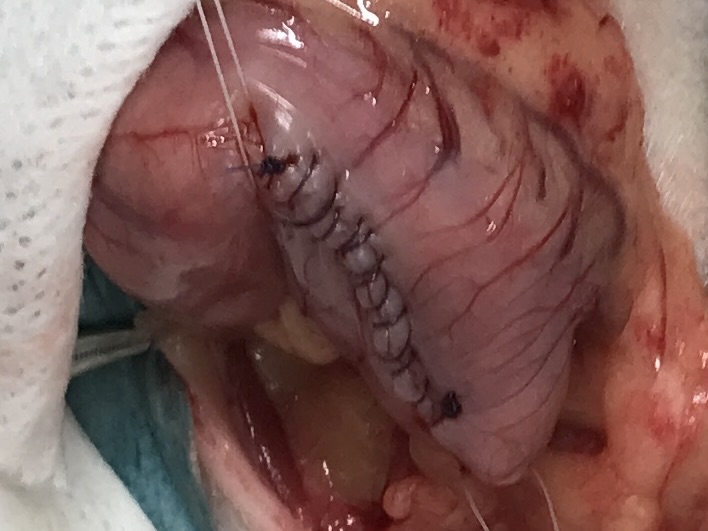

下の写真は胃の縫合後の画像です。